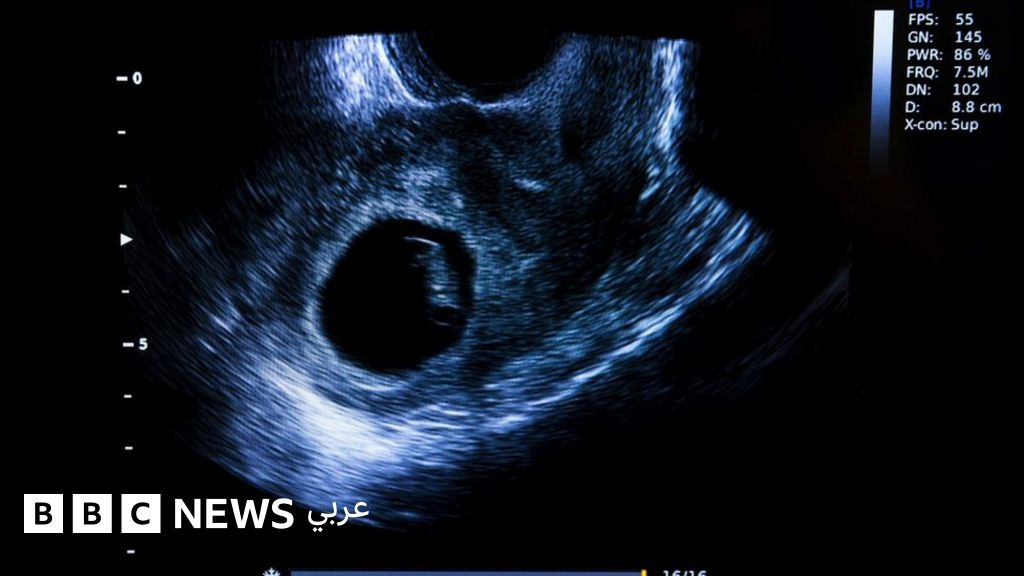

بحسب وثيقة مسربة للمحكمة العليا في أمريكا، قد تفقد ملايين النساء في جميع أنحاء الولايات المتحدة قريبا حقهن القانوني في الإقدام على الإجهاض.

وتشير الوثيقة إلى أن المحكمة العليا تستعد لإلغاء قرار عام 1973 الذي شرع الإجهاض في جميع أنحاء البلاد.

ويقول نشطاء إن حظر الإجهاض لا يوقف العملية من الحدوث، لكنه يجبر النساء على اللجوء إلى أساليب غير آمنة.